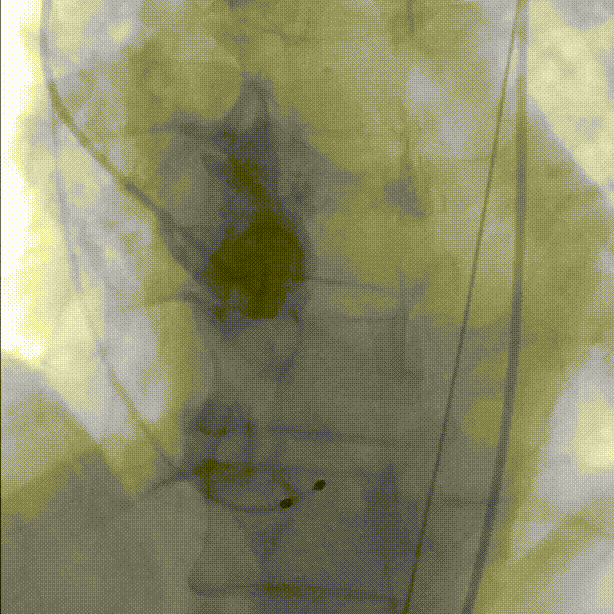

于右室放置起搏导线。超声引导下穿刺外周动脉,左右冠脉造影未见明显狭窄:

主动脉根部造影:

导管测压,压力阶差60mmHg: